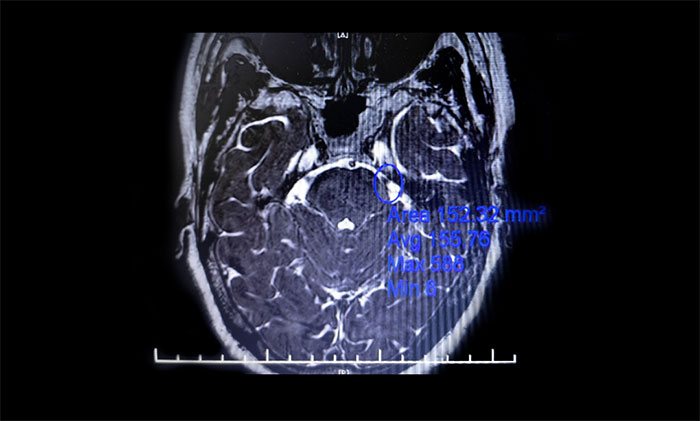

微血管減壓術(shù)是現(xiàn)代神經(jīng)外科典型的微創(chuàng)手術(shù)之一,僅通過患者耳后發(fā)際內(nèi)4-5cm的切口,于顯微鏡下探查三叉神經(jīng)走行區(qū),將所有可能產(chǎn)生壓迫的血管、蛛網(wǎng)膜條索都“松解”開,并將這些血管以Tefflon墊片與神經(jīng)根隔離。一旦責(zé)任血管被隔離,產(chǎn)生刺激的根源就消失了,三叉神經(jīng)核的高興奮性就會(huì)隨之消失,恢復(fù)正常。絕大多數(shù)患者術(shù)后疼痛立即消失,并保留正常的面部感覺和功能,不影響生活質(zhì)量。

▲ 左側(cè)三叉神經(jīng)與周圍小血管關(guān)系密切